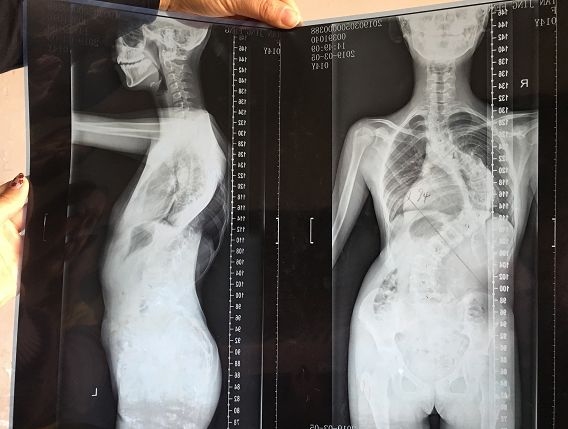

第二天,家人便帶著譚景鳳去往了醫(yī)院檢查。經(jīng)檢查,診斷出譚景鳳為重度脊柱側(cè)彎,脊柱呈“S”形,左肩高,腰背部明顯剃刀背畸形,脊柱側(cè)彎曲角達68度。診斷結(jié)果出來后,醫(yī)生建議譚景鳳馬上手術(shù),但家里卻拿不出治療費。

今年3月4日,姑姑譚序容再次將譚景鳳帶到醫(yī)院復(fù)查,復(fù)查發(fā)現(xiàn)她的脊背變形越來越嚴重,脊柱側(cè)彎曲角增加了近30度。如果不盡快做手術(shù),可能會癱瘓在床。